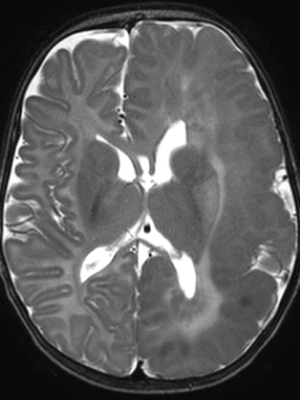

An MRI revealed that Maryam had hemimegalencephaly, a rare neurological condition where one half of the brain is enlarged and can cause epilepsy, developmental delays and muscle weakness. In this case, it had affected the left hemisphere of Maryam’s brain. She was immediately rushed to The Hospital for Sick Children (SickKids).

And at every step, the Interventional Neuroradiology team, Epilepsy and Neurosurgery teams worked together, using detailed electroencephalogram (EEG) and brain MRI scans to ensure precision and safety.

Now, months later, Maryam has not had a single seizure since July 2024.

“She went from having seizures about every two minutes to having one or two per day, to then having zero, which is incredible,” says Muthusami.